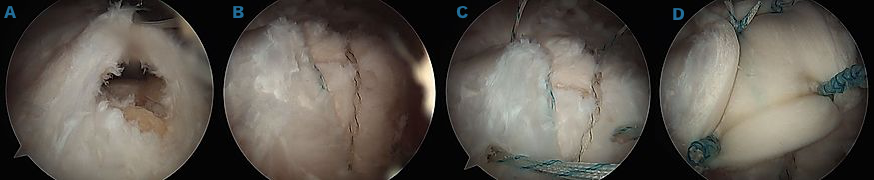

Arthroscopic revision rotator cuff repair

Arthroscopic images of a revision rotator cuff repair using patch augmentation to help with healing.

A) Initial camera image of tear after preparation.

B) Standard repair of the recurrent rotator cuff tear.

C) Four additional anchors placed around the repair to hold down the graft.

D) Final image after graft has been tied down securely over the traditional rotator cuff repair.